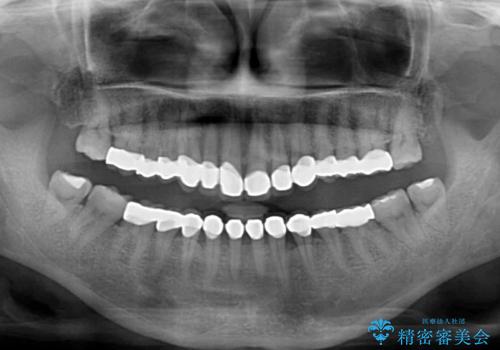

- 前歯の変色や欠損による隙間を気にして来院された患者様です。

上顎前歯は樹脂による変色を覆い隠す処置が行われていましたが、汚れが溜まりやすく厚みも増している状態でした。

上顎前歯は樹脂を外し、下顎前歯の隙間はそれぞれの歯を大きくするように補綴治療を行うことで隙間を埋めることとしました。

口を開けたときに見える範囲をオールセラミッククラウンとし、とても自然な口元に仕上げることができました。